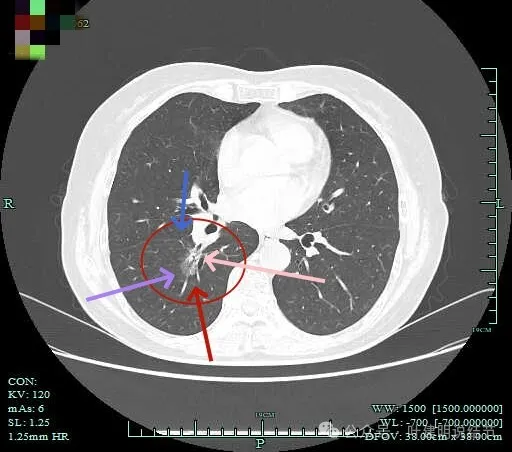

实性成分较多,边缘毛刺。

毛刺征明显,而且是短毛刺且锐利。

毛刺。

边缘区也不光滑,显毛糙。

密度杂乱,毛刺明显,支气管僵硬。

杂乱密度,整体轮廓较清,边缘毛糙。

斜裂根部有增厚并与病灶连着。考虑是肿瘤已经侵及叶间裂。

病灶边缘毛刺明显。

肺磨玻璃结节我们常说瘤肺边界清楚加上随访持续存在,基本上是肺癌性质的。但像今天这种混合磨玻璃密度的病灶,你看它瘤肺边界却是不清楚的,只是整体轮廓相对较清。但它的瘤肺边界是布满细毛刺的,而且是短毛刺且锐利,在影像上就像刺入周围正常肺组织中。这种影像表现的我将它称为“浸润性生长的影像表现”,说明病灶是浸润性病灶,而非原位癌或良性。这样的病灶不宜过度随访,需要及时干预更为稳当。